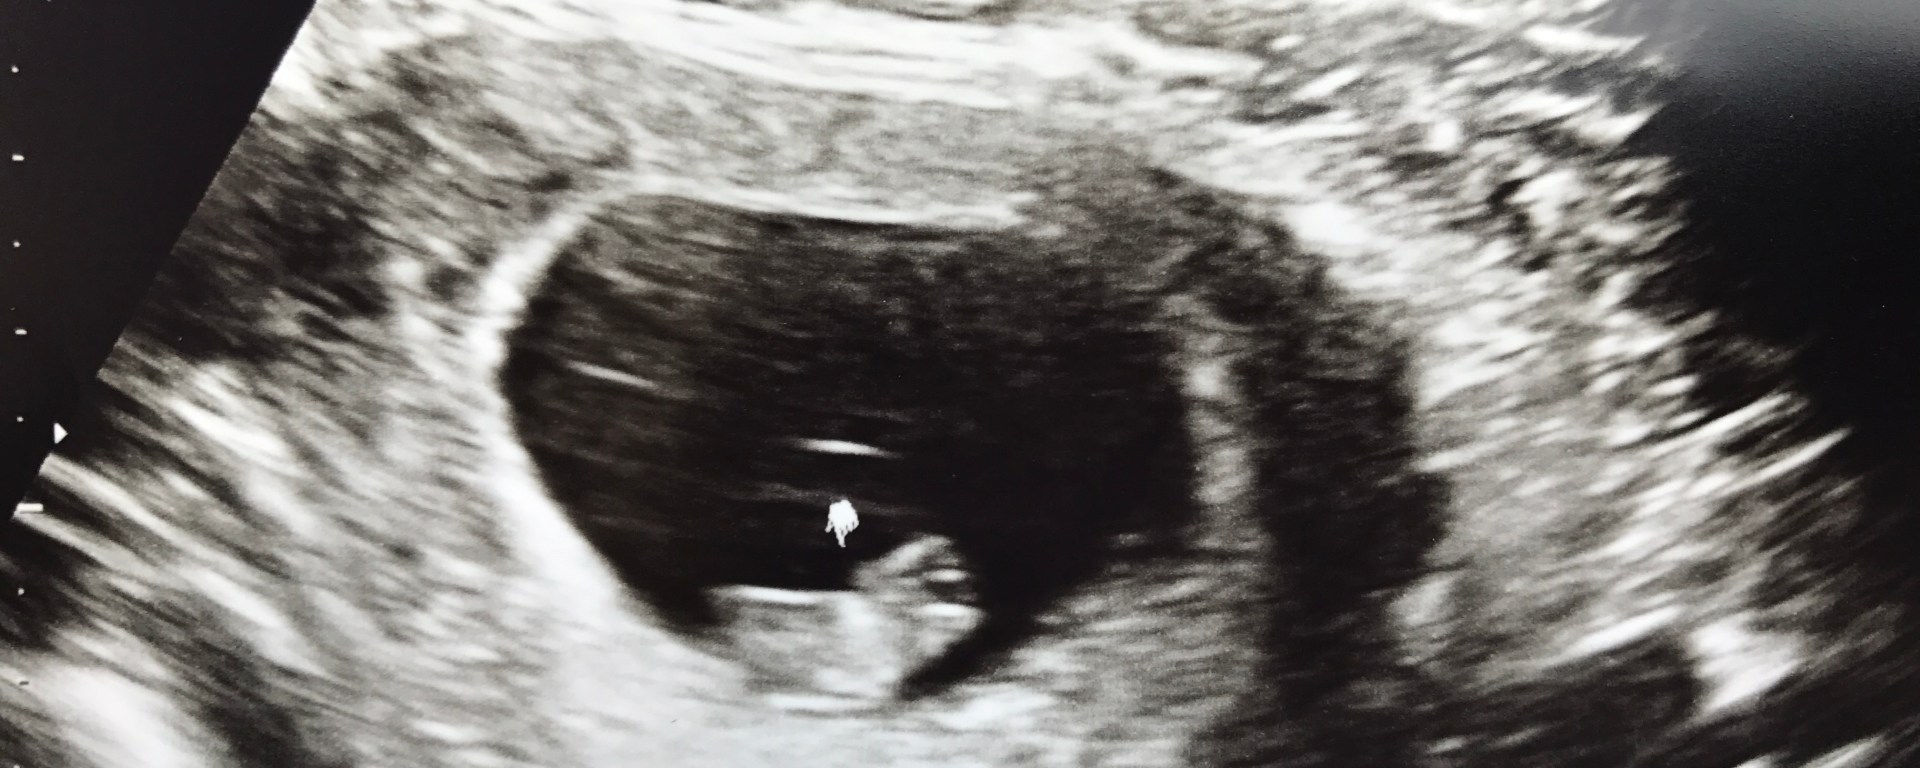

First (left) and Second (right) Ultrasound Photos

FIRST DOCTORS VISIT: Our first doctors appointment was on March 14th, 2017. At this time, they estimated I was 7 weeks and 6 days. We were expecting a big appointment with ultrasounds… but that is not exactly what happened. I walked into my appointment and they asked for a urine sample. Levi and I sat in the waiting room until they called my name. Once my name was called, I had my first appointment with a midwife (not the my doctor that would be delivering our baby). This midwife sat down with Levi and I and asked us many, many questions. Towards the end, she asked, “do you have any questions?” And we replied, “so, did the test confirm I was pregnant….” We wanted to hear it from her. There were chills of excitement from the confirmation she gave us. She then continued to let us know our next steps and inform us that we would be scheduling an ultrasound in order to make sure everything looks good and “to see if there is just one….” I glanced over to Levi as she said these words and his face dropped, “Oh my, I didn’t think about that yet…”

Most Memorable Parts of the First Trimester: Finding out I was pregnant, seeing the first ultrasound, and sharing the news with family and friends.